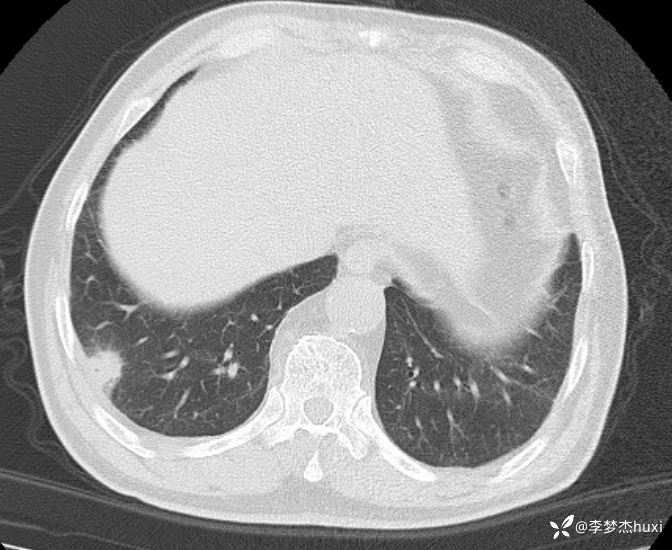

男性63岁,热伴胸痛4天,胸部CT示双肺多发结节,考虑什么疾病?

【现病史及既往史】: 1.患者老年 男,患者于入院前4天无明显诱因出现发热,具体体温不详,伴右侧胸痛,无放射痛,偶有咳嗽、无明显咳痰,无鼻塞,无咽痛,无胸闷、憋气,无恶心、呕吐,无腹痛、腹泻,无尿急、尿频、尿痛,院外口服退热药物治疗(具体不详),症状好转,今患者及家属为进一步诊治前来我院就诊,门诊查胸部CT:双肺炎症;双肺间质性改变;右肺上叶肺大疱?纵隔内肿大淋巴结,部分钙化;主动脉及冠状动脉壁钙化;双侧胸膜局部增厚;右侧第9、10肋骨欠规整?;右侧胸壁术后改变,双肺实性结节,建议复查或肺结节门诊检查,故门诊以“社区获得性肺炎,非重症”收入院。

【临床诊断】: 社区获得性肺炎,非重症。